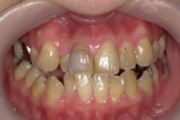

部分矯正症例

40代 女性

費用や期間の面で、全体矯正治療ができない方には、部分矯正治療を行う事も可能です。

ただし、追加でセラミック治療が必要になる場合もあります。

部分矯正治療費:54,000円

ジルコニアセラミック:108,000円(1本当たり)

矯正前

右上の前歯に、凸凹があり、むし歯で変色していました。

矯正中

右上の前歯3本に、透明なブラケットと白いワイヤーで部分矯正をしました。

矯正後

約4か月後には、前歯の咬み合わせが改善し、ジルコニアセラミックで、綺麗な前歯にしました。